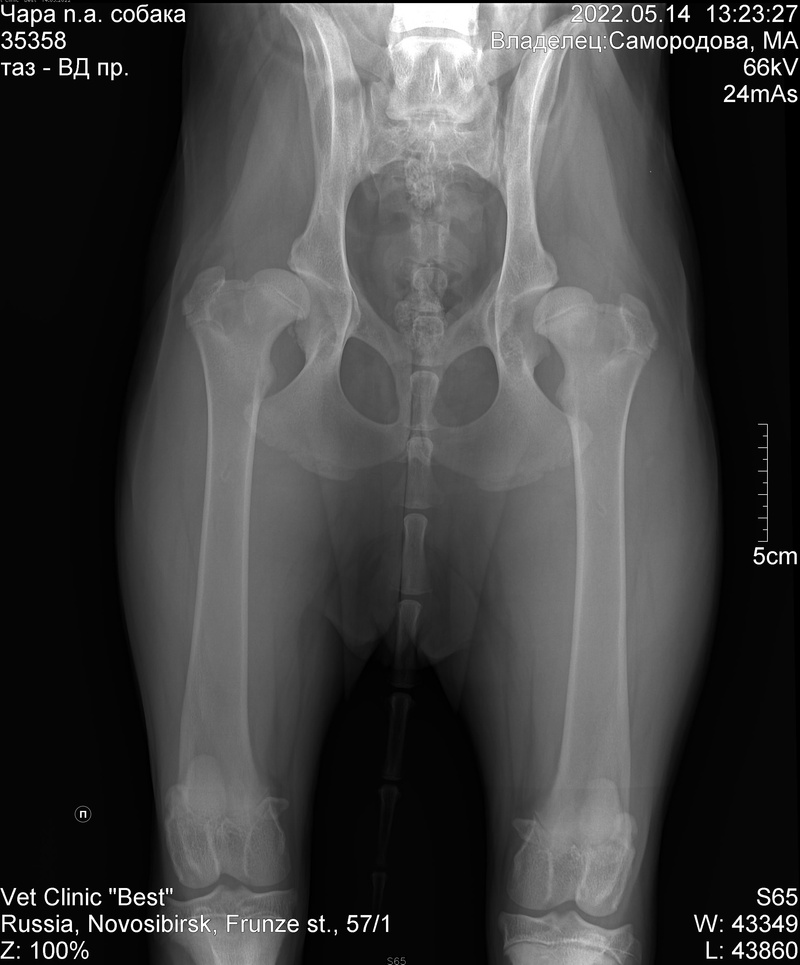

Нашли специалиста (по рекомендации врача РКФ), сделали снимок. Диагноз: терминальный остеоартрит тазобедренных суставов на фоне двусторонней дисплазии ТБС. Первый вопрос, который мы задали – есть ли в этом наша вина и могли ли мы это избежать? Три специалиста нам ответили – нет, это врожденное, без вариантов.